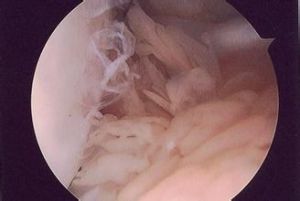

4:實驗室檢查在顯微鏡下絨毛表面為數層滑膜細胞,其中心為少許纖維組織擴張的毛細血管和少量炎性細胞,細胞內外可見含鐵血黃素顆粒結節,由密集的滑膜細胞組成胞漿少胞膜,不清楚核染色較深,在密集的細胞中可見裂隙和乳頭滑膜細胞之間偶見多核巨細胞和泡沫細胞。

將病變滑膜徹底切除。術後應輔以放療,以防止復發。